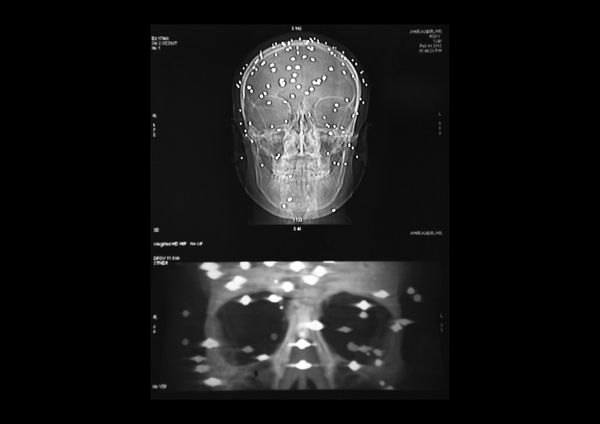

A visual investigation about the disastrous effects of the pellet guns used by the Indian army and the police forces in the Valley of Kashmir, India.

According to a UN report released in 2018, the new weapon is responsible for blinding around 1000 people and killing dozens.

Carrying dozens of pellets in their bodies, victims face unknown long term health consequences.